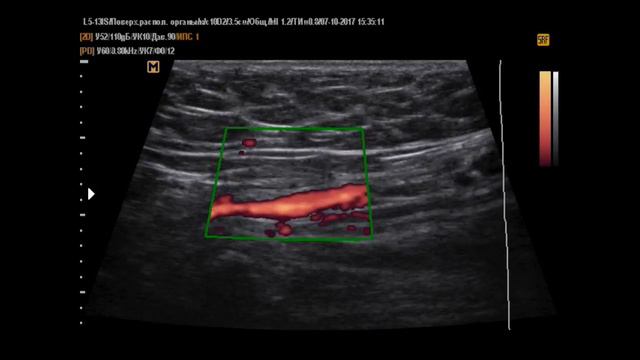

Фуникулоцеле 2 у мужчины 50 лет.,